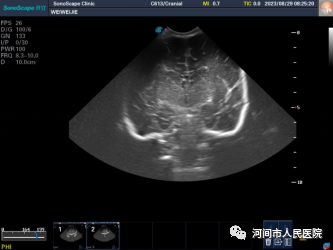

▲新生儿室管膜下囊肿